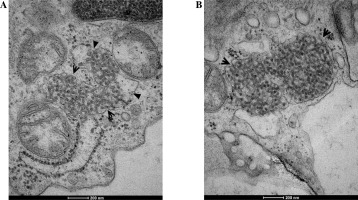

The evaluation of the biopsy samples in a light microscope revealed class III LN in five cases (50%), class II in three cases (30%), and class IV and class V in two individual cases (Table 1). Ultrastructural analysis of the biopsy material showed the presence of TRIs in seven patients (Table 3). These structures were most often found in endothelial cells of both the vascular bundle and the peritubular capillaries. They were occasionally observed in monocytes within capillaries and mesangial fields (Fig. 1). TRIs occurred within the irregularly widened cisterns of the endoplasmic reticulum. Some of them presented signs of pronounced swelling, which led to disruption of the surrounding membranes. In some inclusions, the tubular structures came into close contact with the membranes of the endoplasmic reticulum (Fig. 2). Both the size of the inclusions and the frequency of their occurrence varied among specimens (Fig. 3). The size of the TRIs varied in the range 300-1600 nm. Numerous TRIs (several inclusions in one glomerulus) were found in the biopsy of a patient with class V LN. All patients were tested for the most common viral infections connected with presence of TRIs (HIV, HBV, HCV, EBV, CMV) and all those disorders were excluded by performing simple blood tests. Only in one patient, after three years of treatment, was the re-biopsy performed. TRIs were still present in the specimen, but they were much less abundant (Fig. 4). In three cases with the highest presence of TRIs, the disease began before puberty (at 8-10 years of age), and in all these cases hematological disorders such as leukopenia, anemia, and thrombocytopenia preceded the LN diagnosis. Inclusions in a typical location, near subendothelial deposits, were observed in only one patient (Fig. 5). Biopsies of three patients with disease onset in adolescence (around 14 years of age) revealed no TRIs in the sampled material. In these patients, arthritis and nephrotic proteinuria dominated the clinical picture.

Fig. 3

Fragment of a capillary with a highly swollen endothelial appendix containing three tubuloreticular inclusions (TRIs) (arrows) in renal biopsy samples collected from patients with juvenile systemic lupus erythematosus (jSLE)